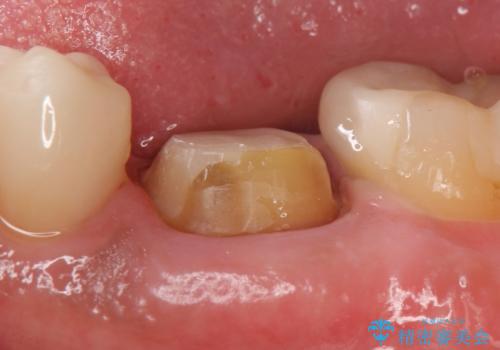

- 左下6番目の銀歯をオールセラミッククラウンにやり替えた症例です。

根管充填が不十分だったため再根管治療も行っております。

- オールセラミッククラウン…¥100,000、仮歯…¥10,000、ファイバーコア…¥20,000費用は治療当時の料金となります